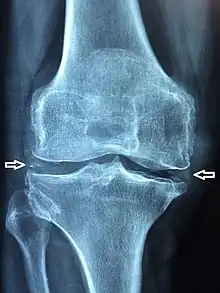

| X-ray of a knee with chondrocalcinosis | |

Chondrocalcinosis or cartilage calcification is calcification (accumulation of calcium salts) in hyaline cartilage and/or fibrocartilage.[1] Chondrocalcinosis is an observation that can be visualized through diagnostic imaging tests such as X-rays, CT, MRI, and ultrasound.[2]

Chondrocalcinosis can be visualized on projectional radiography, CT scan, MRI, ultrasound, and nuclear medicine.[1] CT scans and MRIs show calcific masses (usually within the ligamentum flavum or joint capsule), however radiography is more successful.[1] At ultrasound, chondrocalcinosis may be depicted as echogenic foci with no acoustic shadow within the hyaline cartilage.[12] As with most conditions, chondrocalcinosis can present with similarity to other diseases such as ankylosing spondylitis and gout.[1]